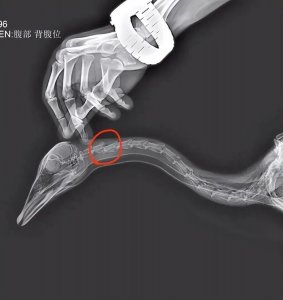

• ​网红“大宝”死亡,“已交由公安处理”

网红“大宝”死亡,“已交由公安处理” 6 月 22 日,在河北石家庄, 有网友发视频称, 网红大雁 大宝 被游客踢中, 造成颈椎第二节骨折, 救治无效后死亡。 当事游客称大雁吓着孩...